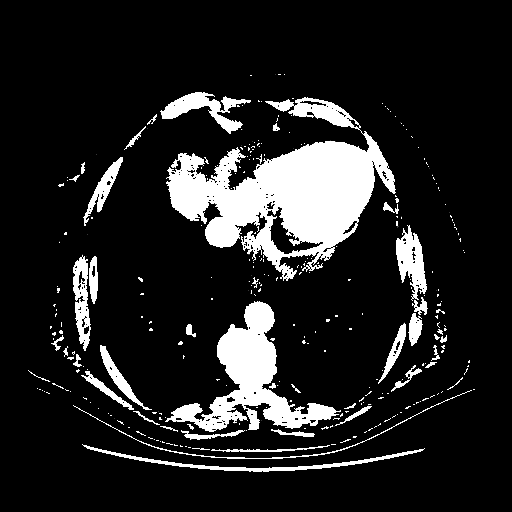

Generated VENOUS CT scan (A→B translation)

Full window (WL 1023.5, WW 4095 β†’ Low βˆ’1024, High +3071)

Actual HU range: [-1024.0, 3071.0]